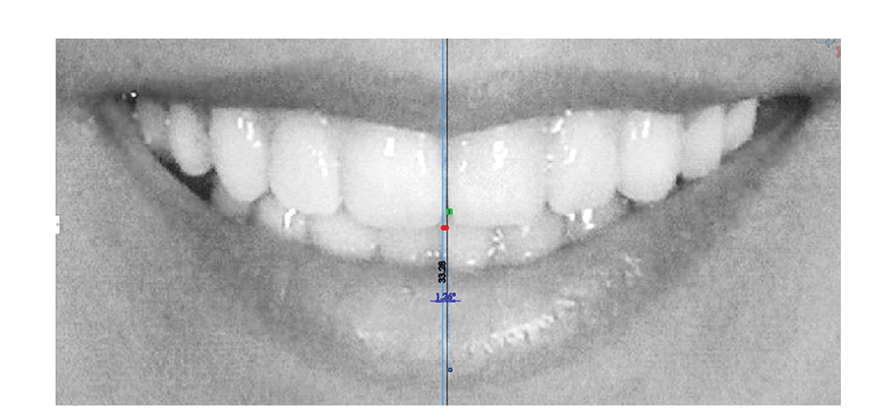

A tactile line at the contact area of the upper central incisors was designated as the upper dental midline. After magnifying the photo, its position relative to the smile midline (the template midline) was measured in tenths of a millimeter using Solidworks® software . Furthermore, the angular deviation between the upper dental midline and the smile midline was measured in tenths of a degree using the same software (Figure-1).

Figure 1. Evaluation of upper dental midline relative to template (face) midline